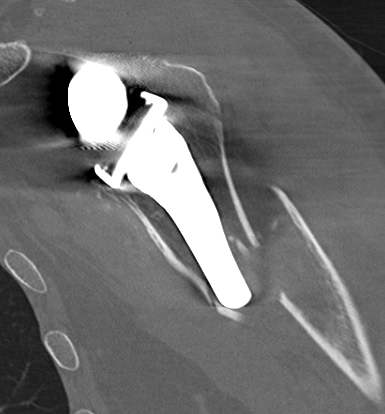

CT acromial stress fracturesCT Acromial Stress Fracture Reverse TSR

CT demonstrating acromial stress fracture